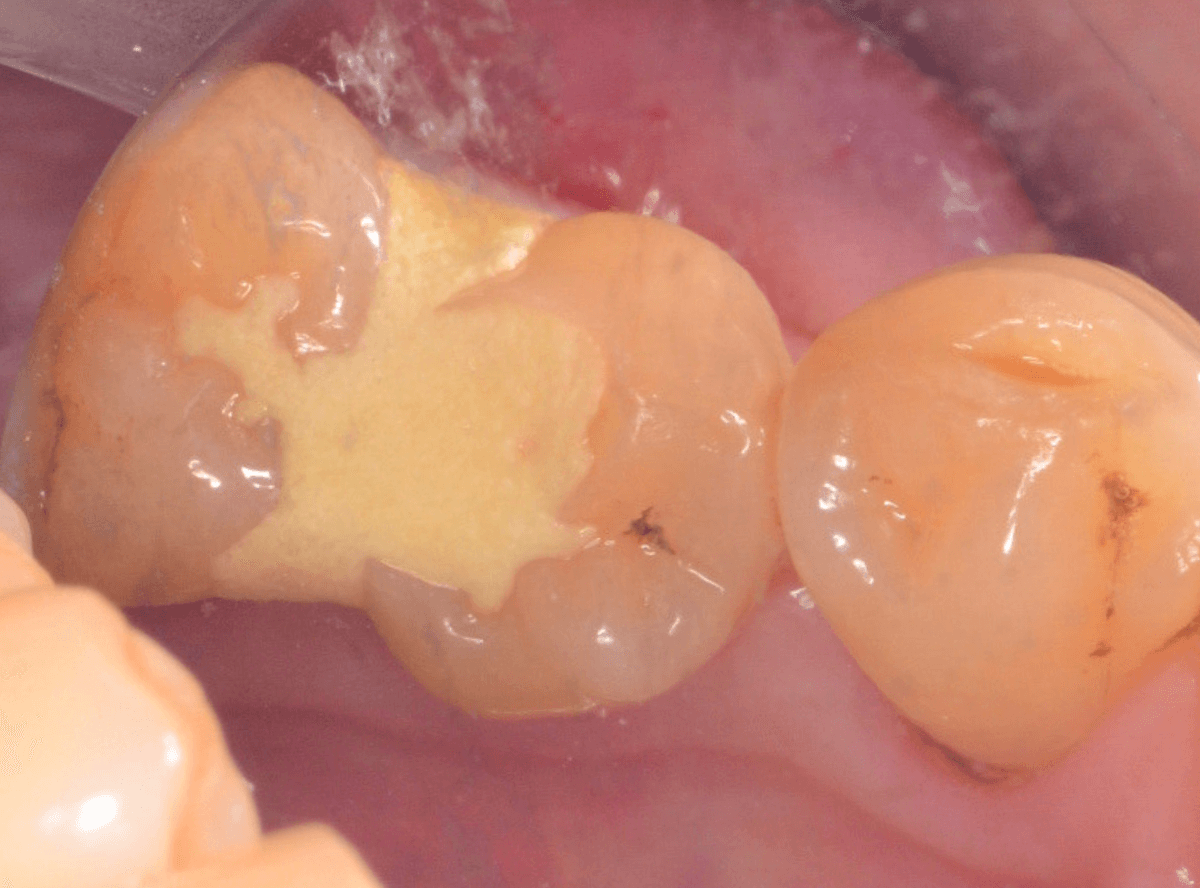

虫歯の治療を開始します。

隣の歯とのすき間を中心に広い虫歯になっていました。

虫歯治療後、特に症状もなく経過観察できましたので、つめものを作る治療に入ります。

セラミック治療をご希望されましたので、

小臼歯をE-MAX・インレー、

大臼歯をジルコニア・インレーで処置することになりました。